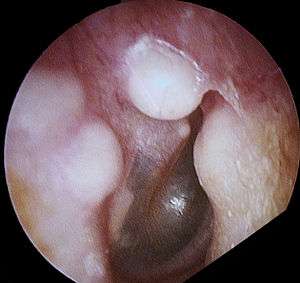

| Osteoma of external auditory meatus | |

An osteoma (plural: "osteomata") is a new piece of bone usually growing on another piece of bone, typically the skull. It is a benign tumor.

Osteoma represents the most common benign neoplasm of the nose and paranasal sinuses. The cause of osteomata is uncertain, but commonly accepted theories propose embryologic, traumatic, or infectious causes. Osteomata are also found in Gardner's syndrome. Larger craniofacial osteomata may cause facial pain, headache, and infection due to obstructed nasofrontal ducts. Often, craniofacial osteoma presents itself through ocular signs and symptoms (such as proptosis).[1]